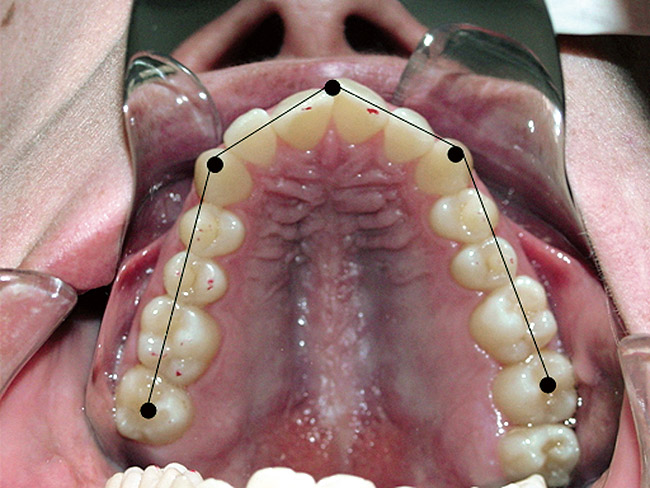

Generally with problems related to growth and development, such as bottle feeding, mouth breathing, tonsils, adenoids, and tongue thrusting,10 the maxilla shows a deep palatal vault and a V shape indicative of an unexpanded maxilla (Figure 1). All of these problems affect the maxilla, which then affects the way the mandible fits within its confines. This is similar to the maxilla acting as a “fence” or corral in which the mandibular teeth are the sheep. If the maxilla is constricted, then the mandibular teeth will crowd to accommodate to the space allowed by the maxillary teeth. The occlusal fencing concept is based on a structural maxillo-mandibular concept rather than a dental concept of occlusion. It takes into account 3-dimensional positioning in space.

Figure 1  The maxilla shows the space allowed  for the mandibular arch. The palatal of the incisors  and canines and the fossae of the posterior teeth  are the limits for the lower teeth to function within.  If the mandible is not in a V form, then the mandible  has to remain retruded in what ends up as a class  II deep bite. This maintains the condyles in a  retruded closed pack position.

Figure 1